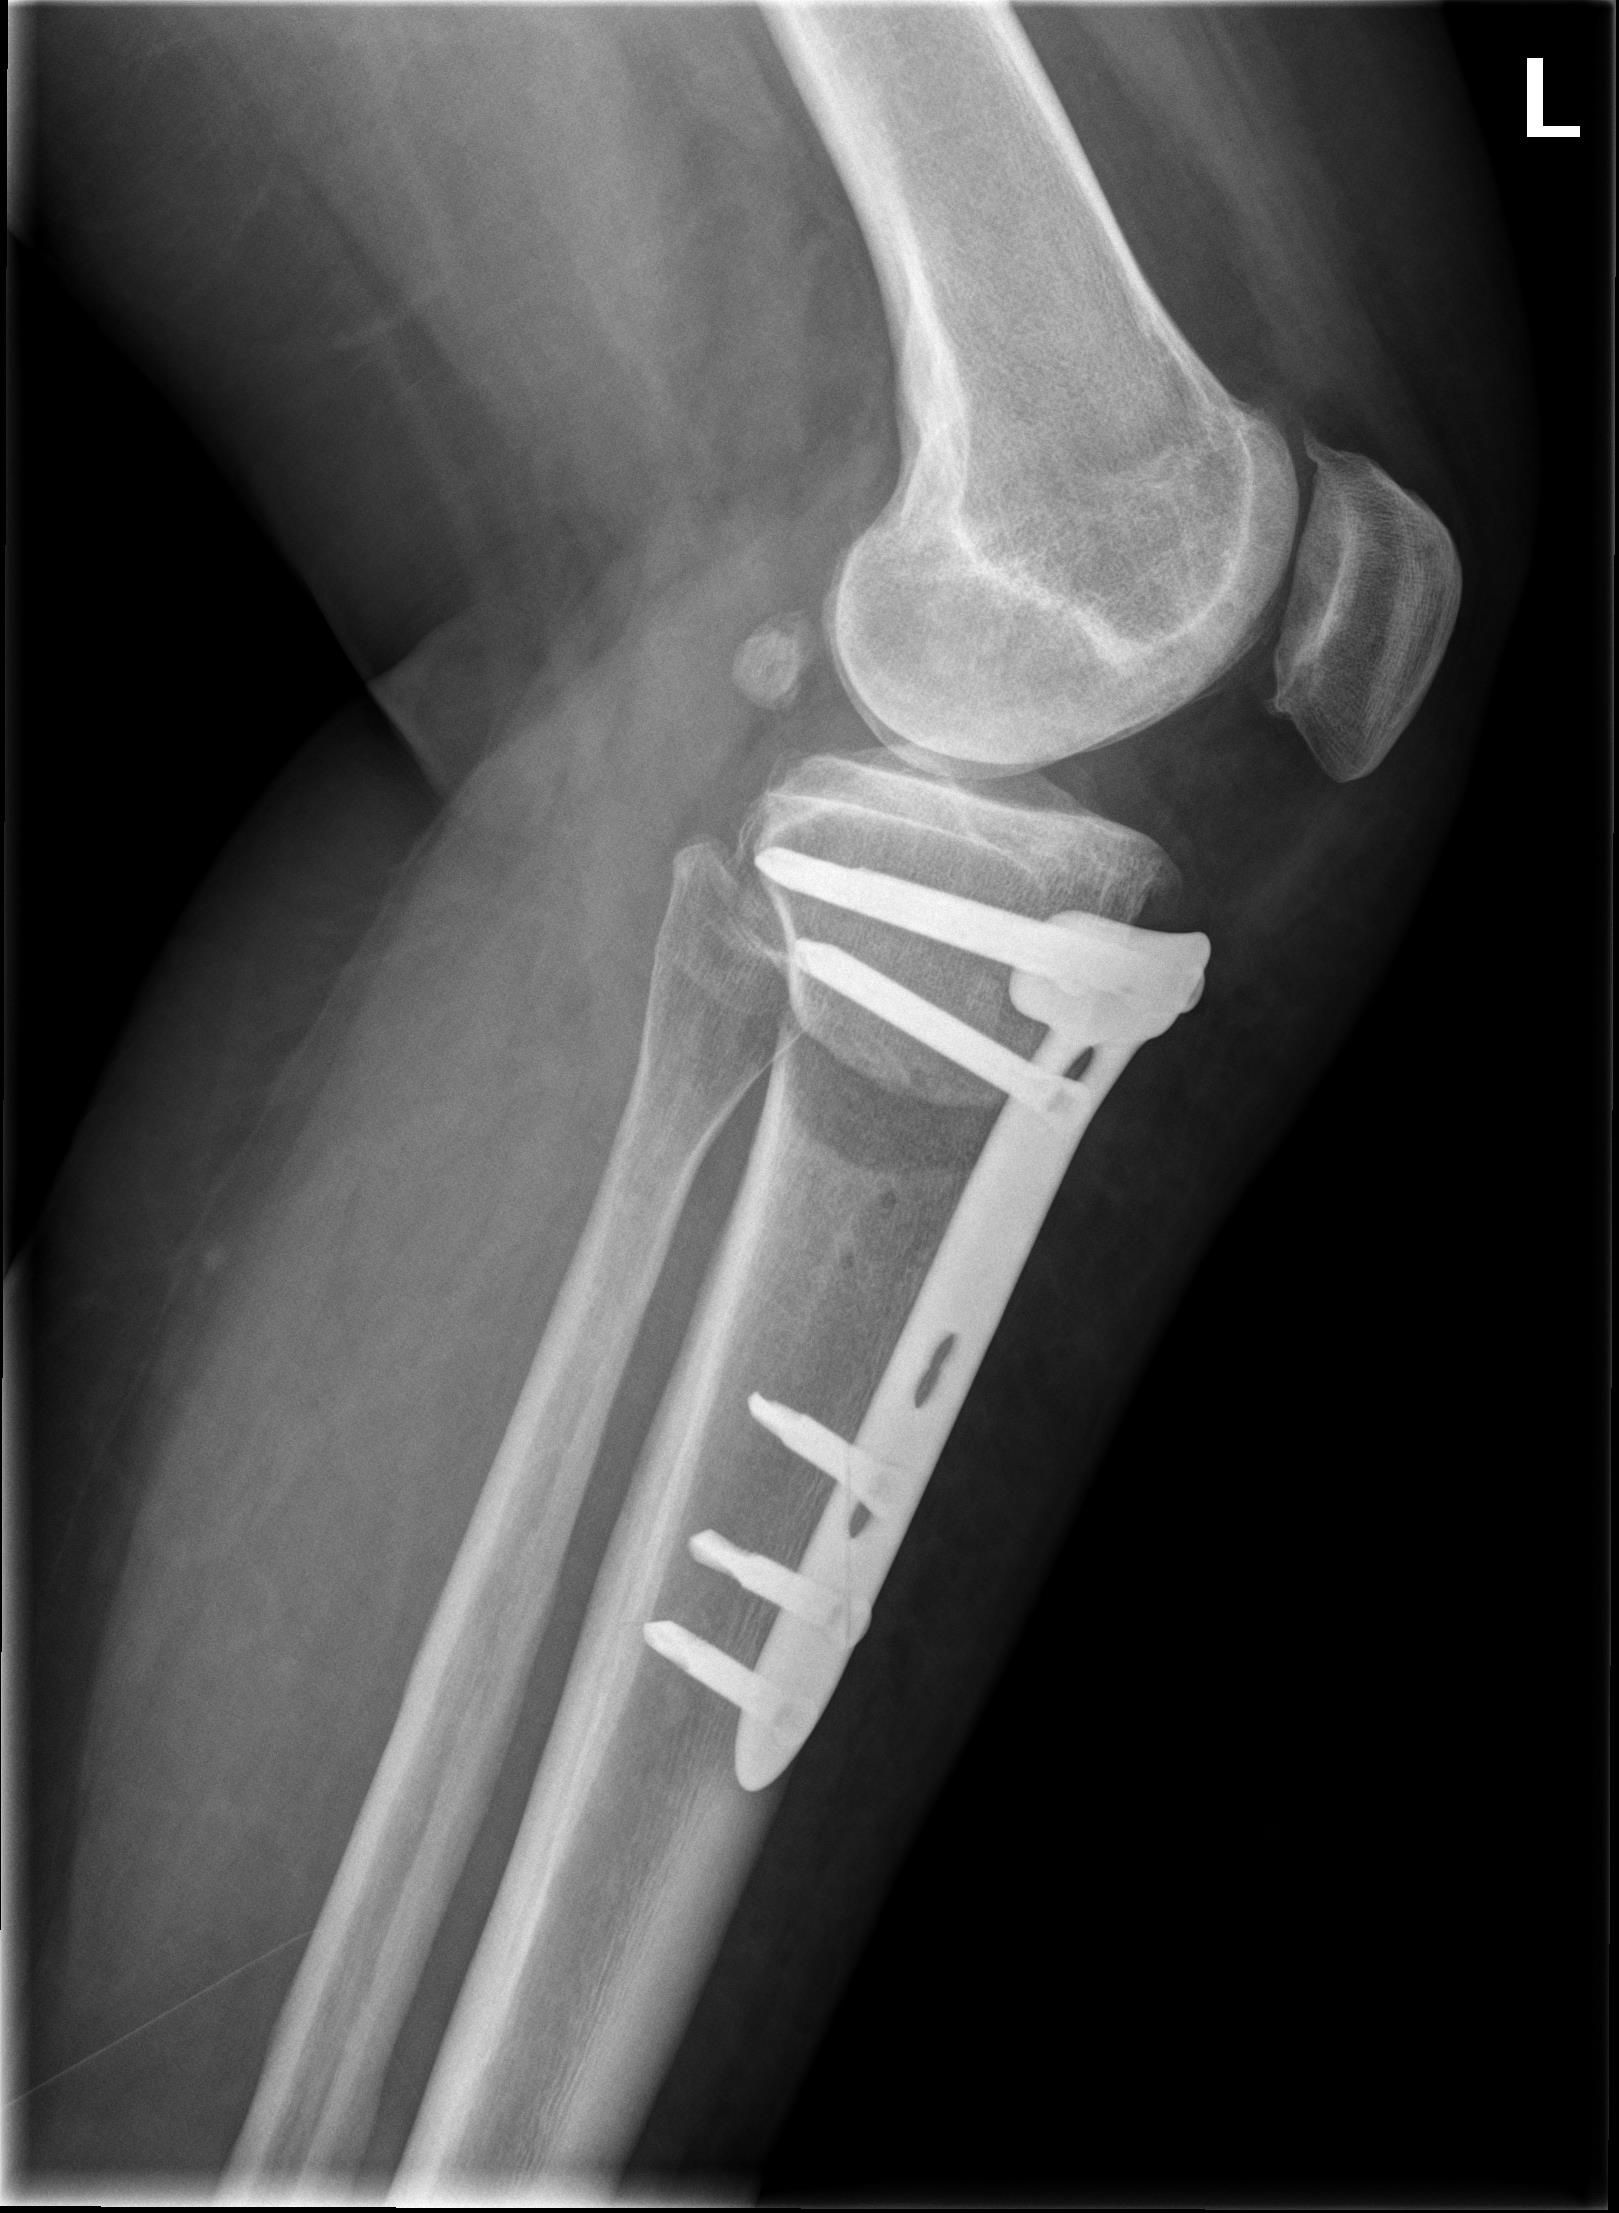

Patient A 53-year-old female patient presented at the emergency department with a locked left knee. The locking occurred whilst sitting in a chair in a flexed knee position. She was unable to unlock her knee due to the pain. On examination the knee was swollen and locked in a 70° flexion angle. An X-ray of the knee showed an inferior patellar dislocation without fractures (figure 1). Six years earlier she was treated with a medial open wedge HTO (OWHTO) with a proximal tuberosity osteotomy with a locked plate for valgus correction of medial compartment osteoarthritis. During surgery a planned 9° correction was performed. Insall-Salvati ratio (ISR) pre-operatively was 0.89. Directly after surgery ISR was 0.83 (figure 2, figure 3). Her postoperative course was uneventful, and the final results were excellent until her recent presentation.

Intervention After administrating analgesics, a reduction was performed by hyperflexing the knee, unlocking the superior patellar osteophyte from the trochlear groove (figure 4.) After two weeks of weight bearing in an extension splint, the patient was advised to resume normal activities. After reduction of the patellar dislocation the X-ray showed an ISR of 0.74. The X-ray also showed a suprapatellar osteophyte.

Comparison Guidelines are lacking, concerning which surgical technique to use for HTO. The latest Cochrane update in 2014 concluded that there is no evidence for selecting a most favourable osteotomy technique.1 Currently, the preferred technique is the medial OWHTO popularised by Lobenhofer in 2003.2,3 The main disadvantage of OWHTO is a change in patellar height.4 Patella infera is a common result after OWHTO with a proximal tuberosity osteotomy (figure 5). Otsuki et al stated that for every 1° correction the Caton-Deschamps index is decreased by 1.7%.5 This unfavourable outcome of OWHTO is well recognised in literature.6 To prevent patella infera Gaasbeek et al. introduced a novel technique of a biplanar osteotomy leaving the tibial tubercle attached to the proximal segment; the distal tuberosity osteotomy in OWHTO7 (figure 6). It resulted in an unchanged patellar height postoperatively.